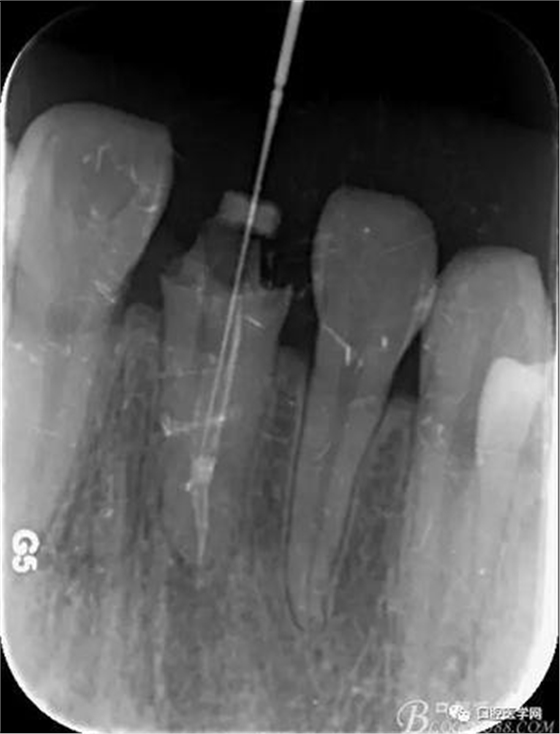

輔助檢查:X線見(jiàn)根尖區(qū)輕低密度影像,根尖1/3見(jiàn)根充物密實(shí)恰填,根管上2/3見(jiàn)折斷纖維樁,與根管密實(shí)。

術(shù)前X線片

樁道長(zhǎng)14mm